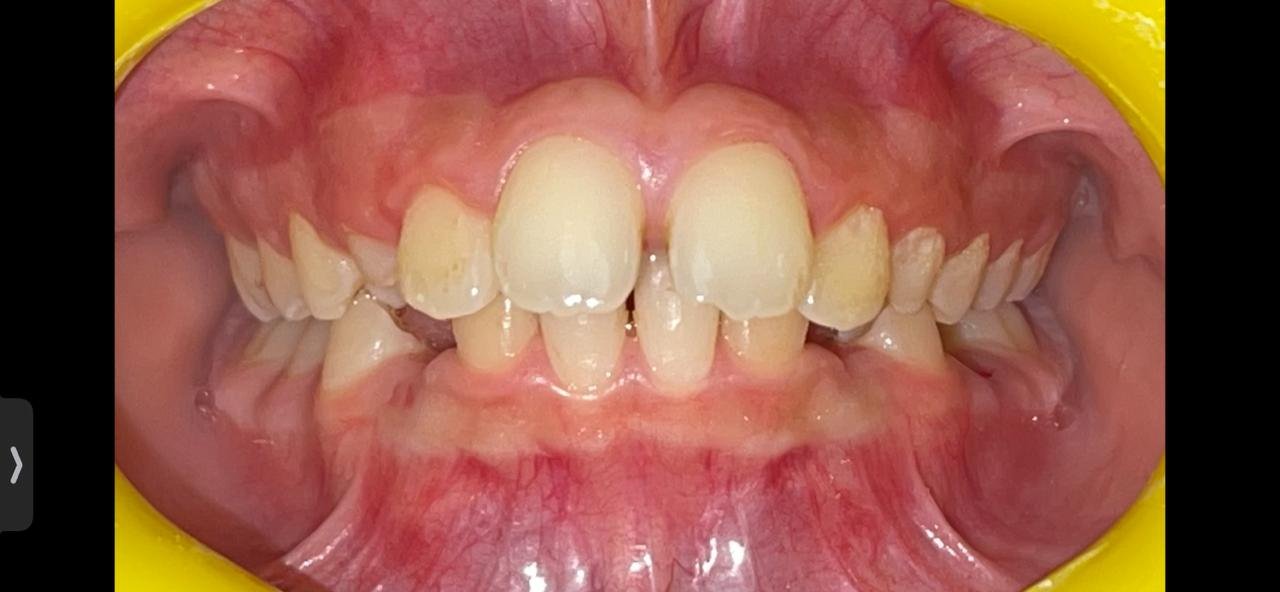

تقويم الأسنان هو أكثر الطرق الطبية استخدامًا لتصحيح إعوجاج الأسنان وعلاج تشوهات الفك، كما أنه يستخدم في علاج وإصلاح مشكلة ازدحام الأسنان وجعلها على صف واحد، بالإضافة إلى أنه يساعد الأطفال في الحفاظ على أسنانهم الدائمة بشكل متناسق وابتسامة جذابة.

هناك عدة حالات بحاجة ضرورية إلى تركيب تقويم الأسنان، وتتمثل هذه الحالات في:

- وجود بروز في الأسنان العلوية.

- عند وجود تزاحم في الأسنان.

- زيادة حجم الأسنان السفلية عن العلوية.

- الفراغات المتواجدة بين الأسنان.